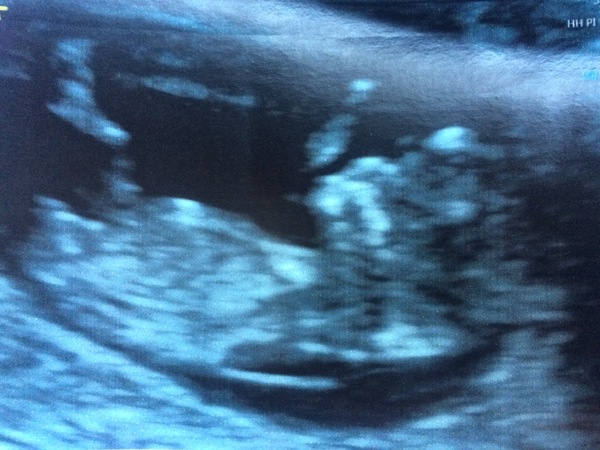

Gender prediction is fun! I have a feeling it's a girl, unsure why. Nub theory potentially says girl, but I'm not quite sure if I'm looking at the nub or a leg grin My husband thinks baby's head looks very boy-like. Skull theory is also a thing, but I can't really see the difference!

What do you think, ladies??

Foxglove88 · 06/06/2017 19:44

It helps if I add the picture! You're not psychic.